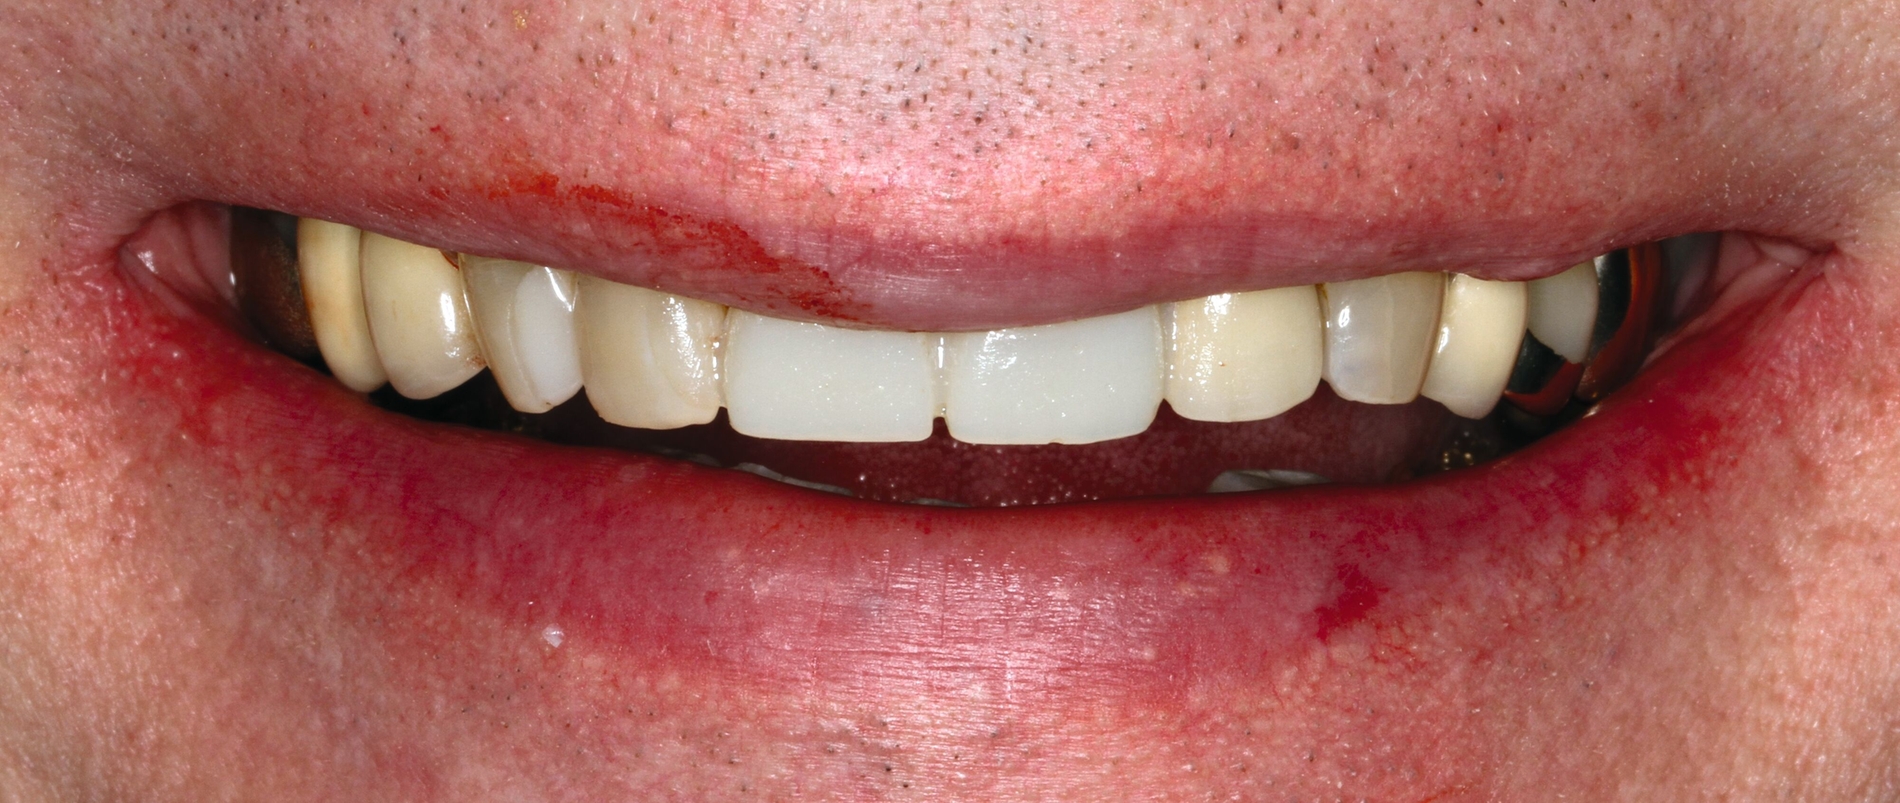

Nach Beendigung der restaurativen Therapie (Abbildungen 11 und 12) wurde dem Patienten zur Schonung der Zahnhartsubstanz und der Restaurationen vor Parafunktionen eine adjustierte Oberkiefer-Aufbissschiene für die Nacht angefertigt. Es wurde ein konsequentes Recall-Programm (nach drei, sechs, neun und zwölf Monaten, danach halbjährlich) realisiert, um die Restaurationen, die Erosionsanamnese sowie die häusliche Mundhygiene zu kontrollieren. Nach zwanzig Monaten Beobachtungszeitraum zeigen sich suffiziente Restaurationen (Abbildung 13). Der Patient ist mit der Ästhetik und der Funktion sehr zufrieden, sein Wohlbefinden hat sich gegenüber dem Ausgangszustand deutlich gesteigert.